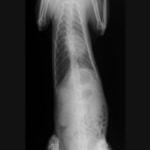

レントゲン画像

・ 胸部レントゲン検査:胸水貯留

■ 症例1 2歳、柴犬、去勢雄

主訴:発咳の頻度増加、努力性呼吸

各種検査結果

・ 血液検査:異常なし(TG:167mg/dL、Tcho:115mg/dL)

・ 心エコー検査:異常なし

・ 胸水の性状:乳白色、TP:5.4g/dL、SG:1.038、TG:>500mg/dL、Tcho:65mg/dL、小リンパ球・好中球主体、細胞数:少ない

・ CT検査(リンパ管造影):無気肺以外の異常なし